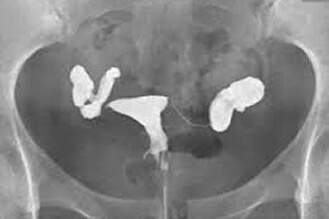

卵管水腫で不通

膣鏡で膣を開き、造影剤注射器を子宮頸部に固定して造影剤を子宮腔内に入れます。2本の子宮卵管が正常ならば造影剤は子宮腔から2本の子宮卵管を通り骨盤腔に流れ込みます。X線撮影により造影剤が骨盤腔に流れたかがわかります。検査過程は約10分です。